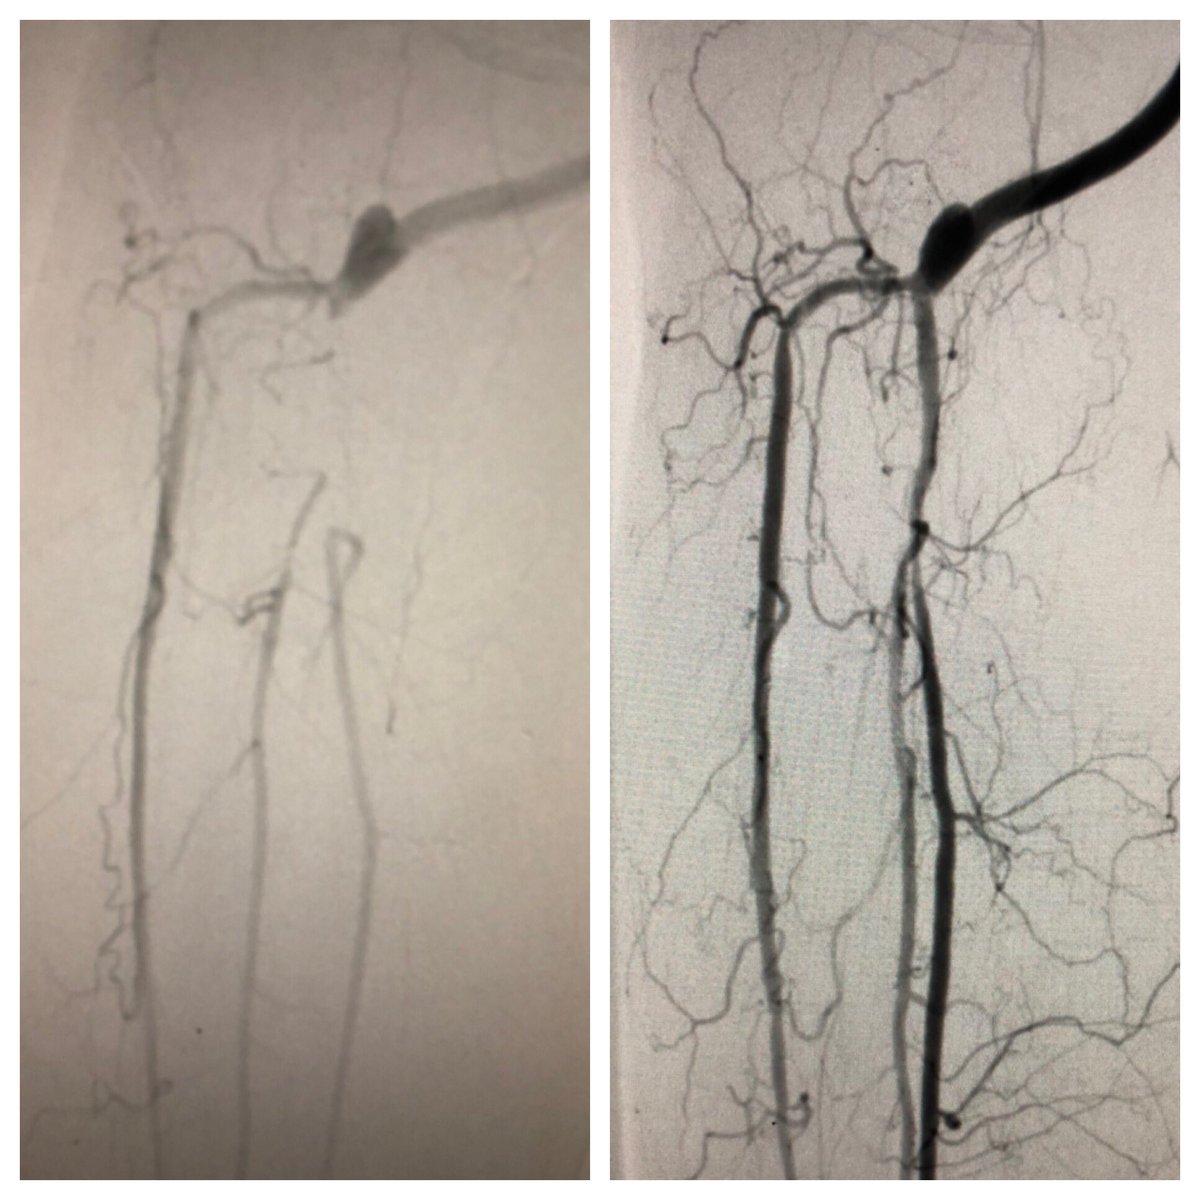

Collaborative approach to treat #CLI patient. VS referral to treat distal AT and TPT after fem-pop bypass. TAMI/dual pedal access for retrograde crossing of previous crushed TPT stent, to protect graft flow into AT & treat distal AT. Merit Ideal (slender) sheaths 3Fr OD #SCAIPAD